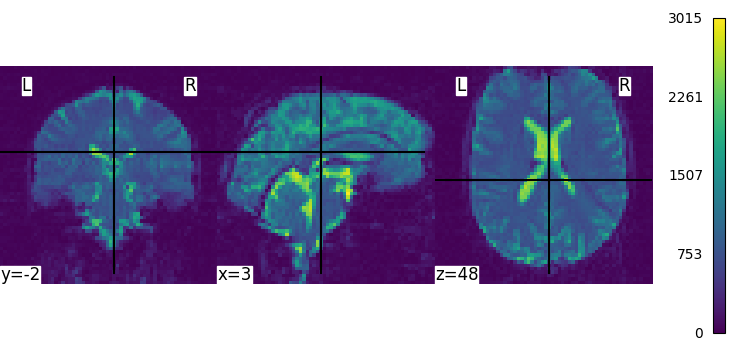

We can display the first functional image and the subject’s anatomy:

from nilearn.plotting import plot_anat, plot_img, plot_stat_map

plot_img(subject_data.func[0], colorbar=True, cbar_tick_format="%i")

plot_anat(subject_data.anat, colorbar=True, cbar_tick_format="%i")

Next, we concatenate all the 3D EPI image into a single 4D image, then we average them in order to create a background image that will be used to display the activations:

from nilearn.image import concat_imgs, mean_img

fmri_img = concat_imgs(subject_data.func)

mean_img = mean_img(fmri_img, copy_header=True)